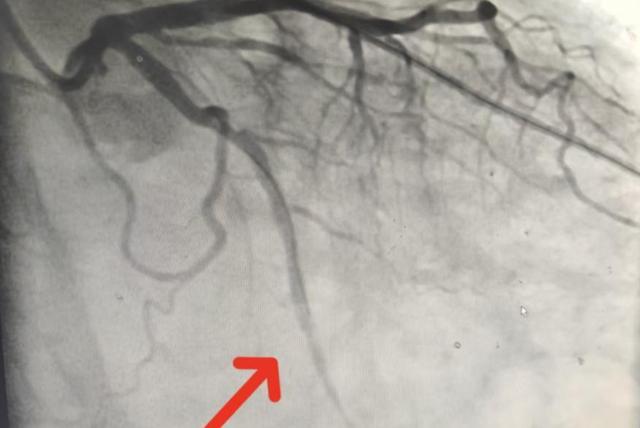

11:37,导丝通过病变血管;球囊扩张;支架精准植入——闭塞的回旋支重新显影,血流恢复3级。

(▲术后患者回旋支远端显影,血流恢复3级。)

从穿刺成功到血管开通,仅用10分钟。